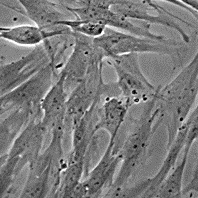

Морфология: фибробластоподобная

Способ культивирования: монослойный